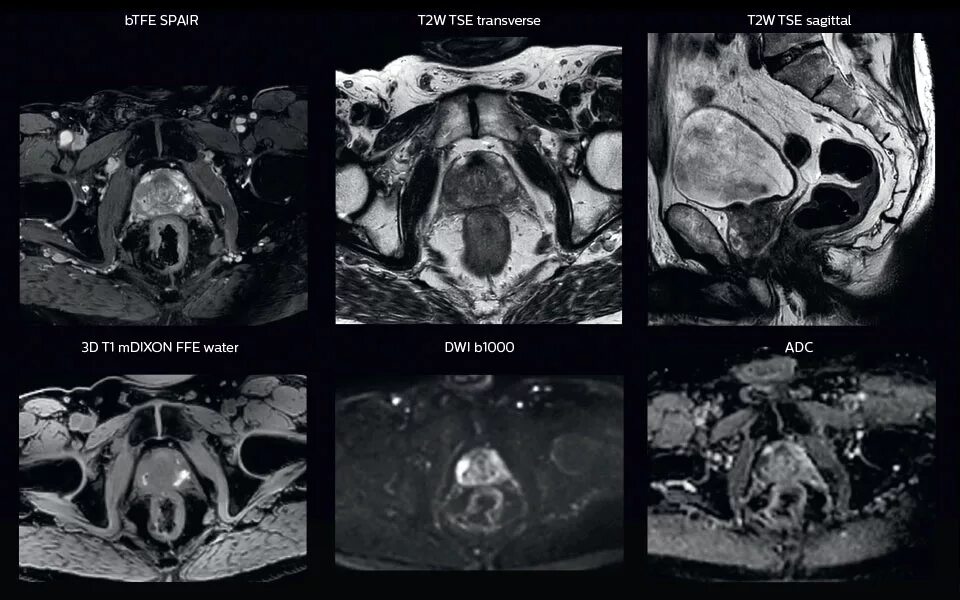

Перед мрт простаты